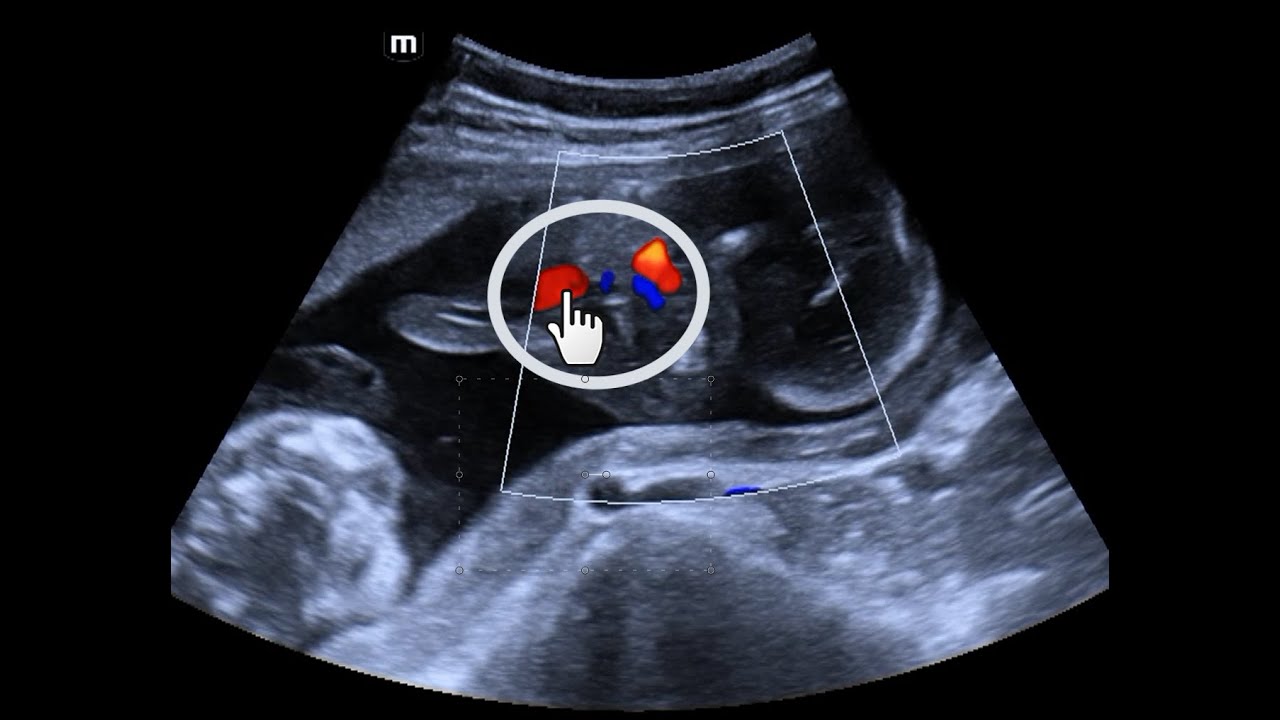

Corresponde ao segmento intra-hepático discretamente dilatado da veia umbilical, identificado como um

curto trajeto intra-hepático no plano abdominal adequado. A visualização apenas da menor extensão possível da veia umbilical, em continuidade com um trajeto lateral em direção ao ramo esquerdo da veia porta (sinal do taco de golfe), confirma que o corte foi realizado ao nível do fígado, evitando planos oblíquos, altos ou baixos, inadequados para a medida da circunferência abdominal.